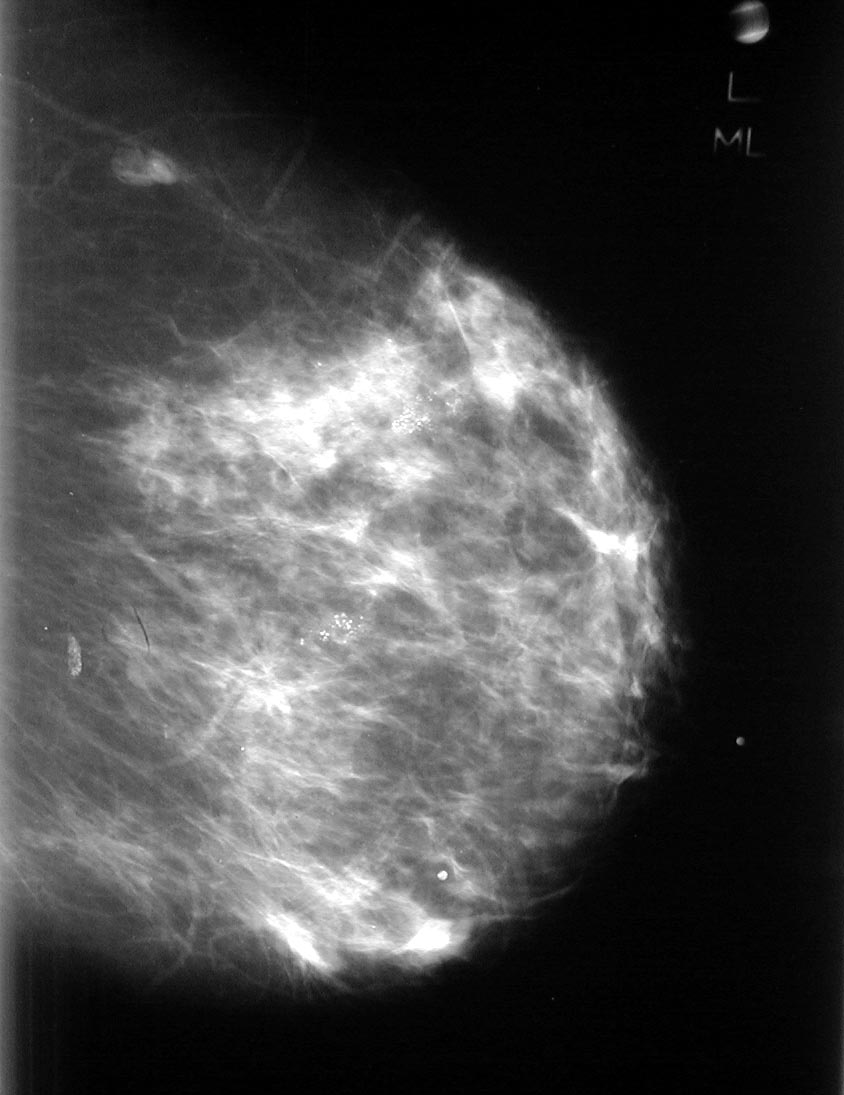

Calcifications

Micro calcifications may be seen on mammography in at least 30% of cases of invasive carcinoma.

They are 1 mm or less and sand like

The calcifications represent necrotic debris